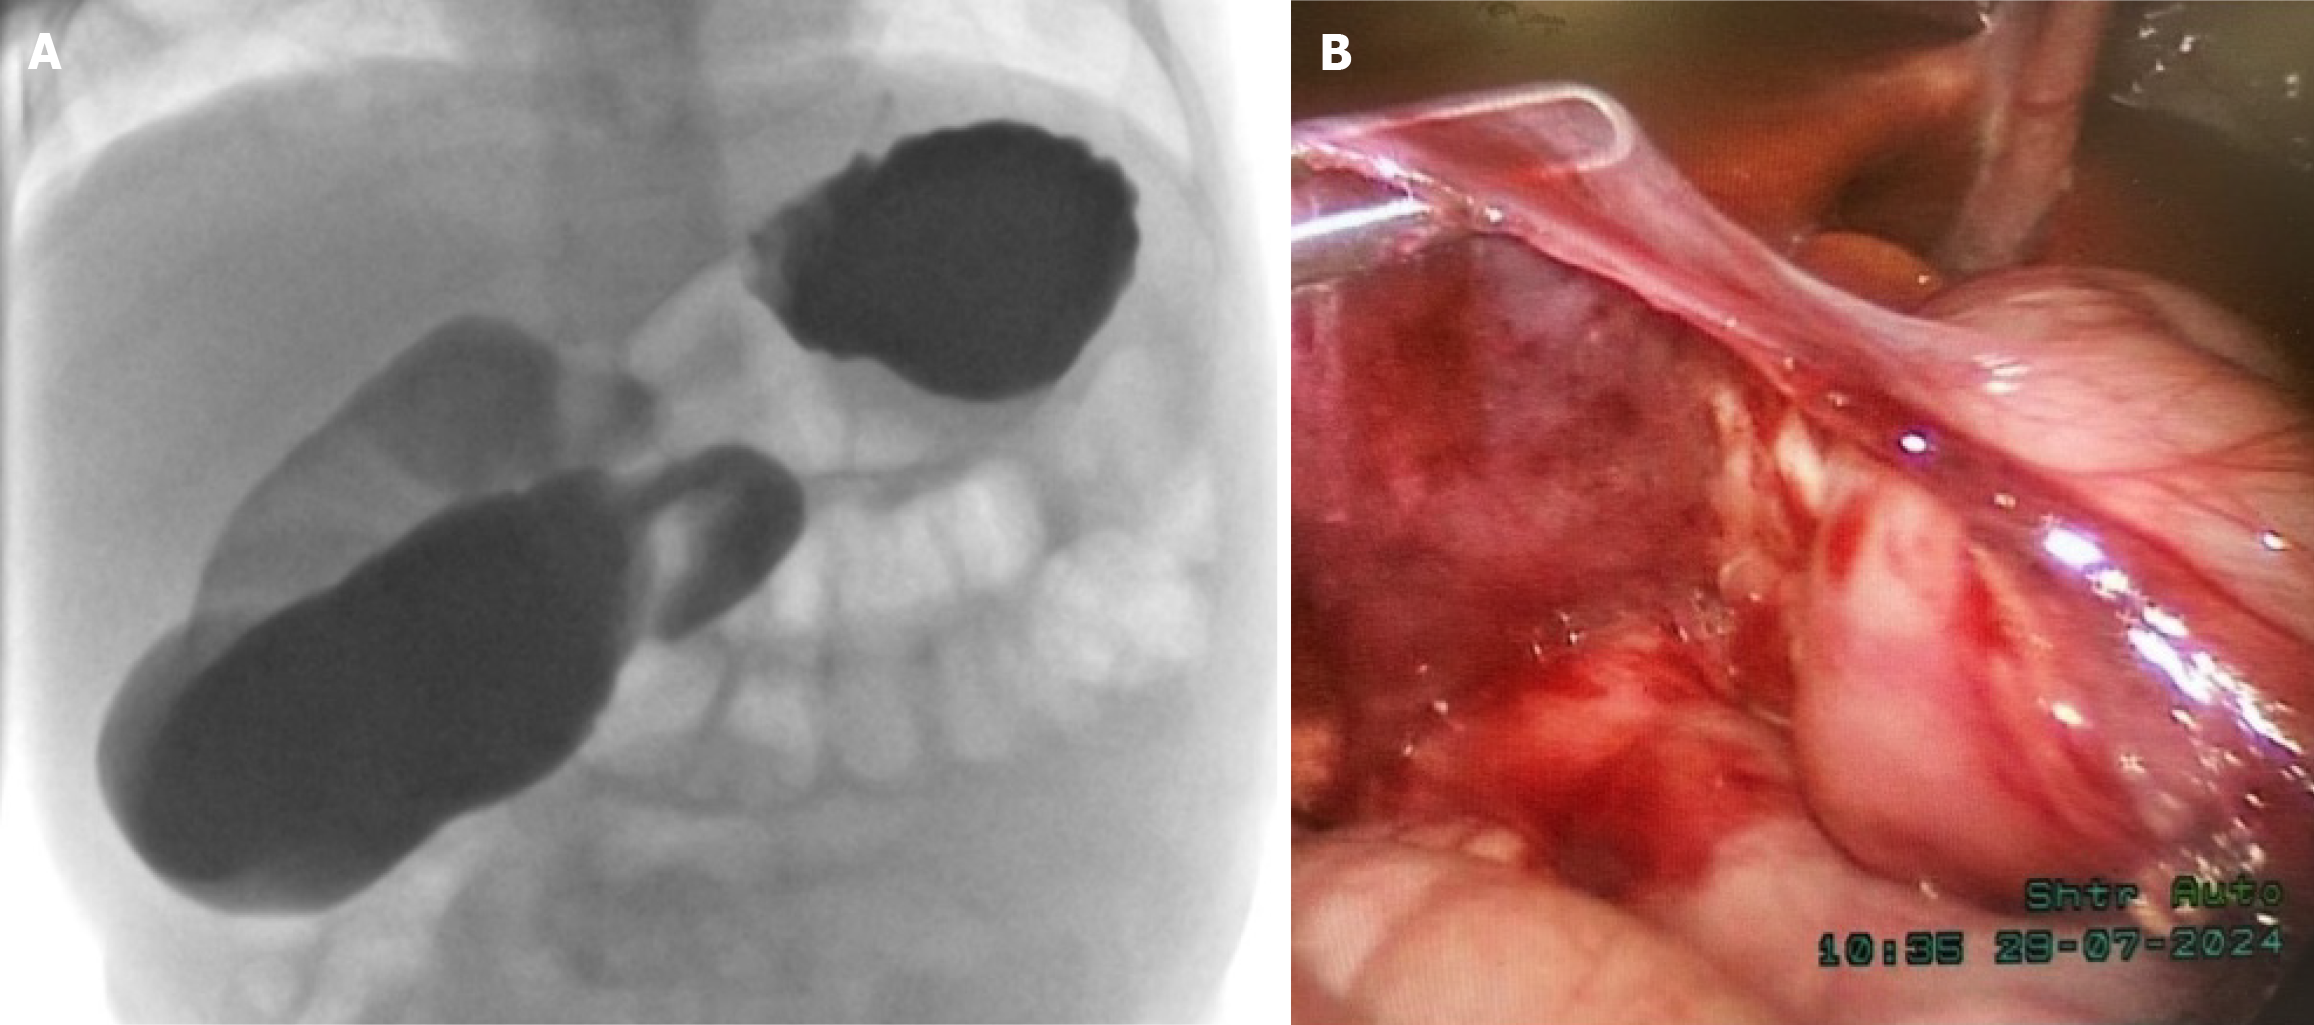

Figure 2 Radiological and surgical images from Case 2.

A: Barium swallow showed contrast passing from the stomach to duodenum with significant dilation to the duodenal jejunal junction, which was located in the midline and did not cross to the left side; B: A laparoscopic Ladd’s procedure was performed. The duodenum was isolated, and the Ladd’s bands were resected.